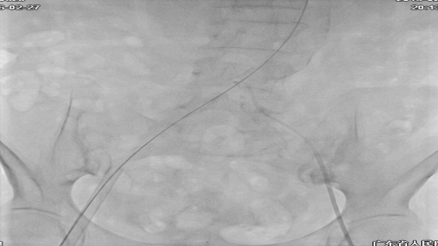

术中DSA:

20F大鞘中DSA发现右股夹层DSA